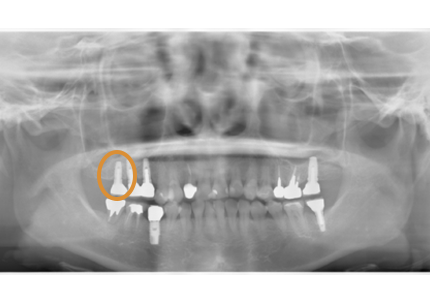

1.初診時口腔内(2007年6月30日)

2.右側上顎洞サイナスリフト後にインプラント埋入

↑ サイナスリフト術前

↑ サイナスリフト術後

3.右上インプラント補綴物装着(2009年7月24日)

↑ 右上サイナスリフト後にインプラント埋入